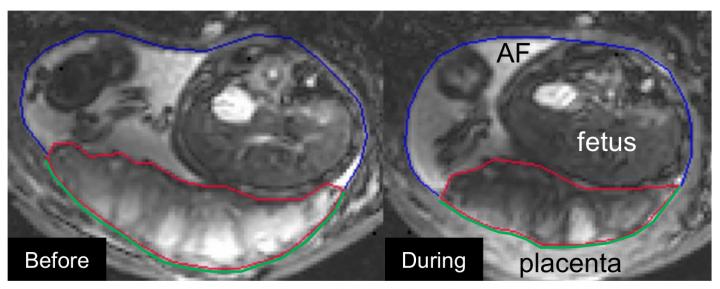

image: Example of the utero-placental pump, left the relaxed placenta before the contraction, right the contracted placenta (the placenta is the area with the red line around it): it's clear how the placenta is smaller during a contraction, pushing out the maternal blood.

The research published today in PLOS Biology also identified a completely new phenomenon which the researchers have termed the 'uteroplacental pump'. This involves contractions of placenta and the part of the uterine wall to which it is attached.

Most excitingly, we also identified a completely new phenomenon which we called the 'uteroplacental pump'. This is a contraction of the placenta and the part of the uterine wall to which it is attached and it is not the same as the well-known Braxton Hicks contractions in which the entire uterus contracts in practice for labour. We now want to work out the purpose of these contractions but we think it might be to stop blood stagnating in parts of the placenta."